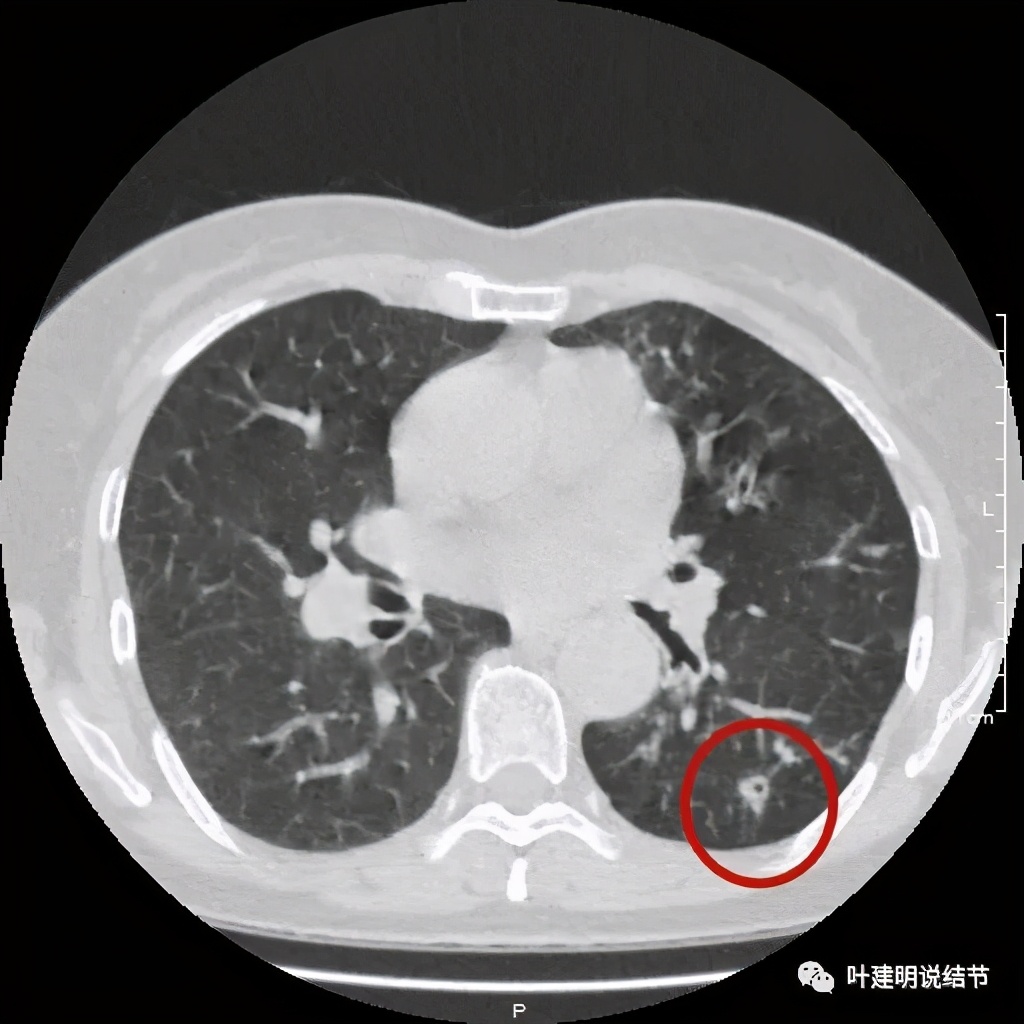

上层见病灶偏实性密度,边缘不光滑

上图见病灶为实性,中间有小空洞,边上有血管进入病灶,靠后侧有棘突样

上图示病灶边缘不光滑,中间有小空洞